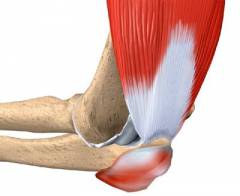

Эпикондилит — воспаление в точках прикрепления мышц к надмыщелкам плечевой кости. Латеральный эпикондилит возникает при поражении внешнего надмыщелка, медиальный — внутреннего.

Основной симптом — боль вблизи локтевого сустава, возникающая при сгибательных и разгибательных действиях. Боль отсутствует в покое и проявляется при пальпации надмыщелков.

Механизм развития эпикондилита связан с длительными перегрузками лучезапястного сустава.

При эпикондилите поражаются точки прикрепления сухожилий мышц к надмыщелкам плечевой кости. Воспаление может проникать в соседние ткани.

При эпикондилите воспаляются участки, где сухожилия мышц сгибателей (медиальный эпикондилит) или разгибателей (латеральный эпикондилит) прикрепляются к надмыщелкам плечевой кости. Эти зоны представляют собой сложные анатомические образования, содержащие костные, хрящевые и фиброзные ткани, взаимосвязанные между собой. Воспаление может легко затрагивать близлежащие ткани, такие как надкостница, костная структура и сухожилия, иногда даже мышцы. Однако ткани локтевого сустава обычно остаются невредимыми.